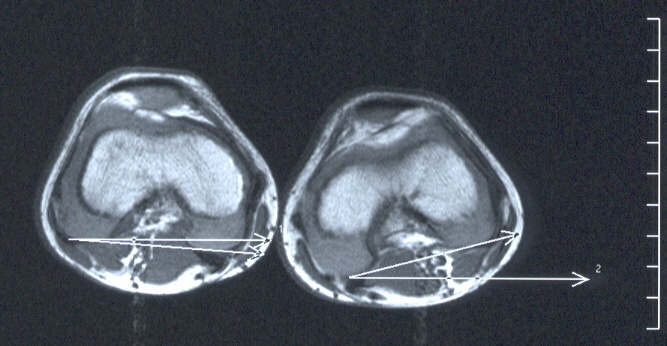

Meistens werden Verzögerungen der Hüft-Drehung, Innendrehfehler der Unterschenkel (Sprunggelenke) und/oder Sichelfüße vorliegen.

USDrehfehler USDrehfehler3 USDrehfehler2

MRT-Untersuchung zur Bestimmung der Drehachsen!